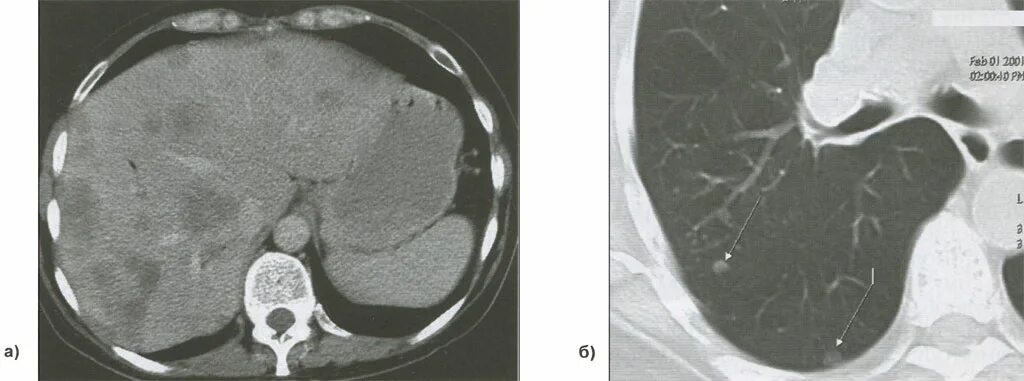

Метастазы в лимфоузлах при раке симптомы